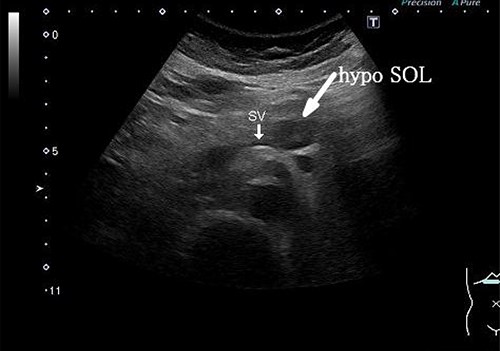

A 58-year-old woman began to have back pain and upper abdominal pain and then visited a hospital. Laboratory findings showed mildly elevated total bilirubin 1.3 mg/dl and high amylase 466 IU/l; however, peripheral blood, liver and kidney functions were within normal limits. Tumor markers were within normal limits: CEA 1.1 ng/ml, CA19–9 24.3 U/ml. An abdominal computed tomography (CT) scan revealed a 2-cm mass with mild contrast effect in the pancreatic body. There was a little tendency to invade the surrounding area, which was different from typical pancreatic ductal carcinoma (Fig. 1). Abdominal ultrasonography (US) showed a 19.4 × 12.6 mm mass in the pancreatic body. It was a hypoechoic mass with a clear boundary, smooth and homogeneous interior. Pancreatic duct dilation was observed more clearly than around the mass (Fig. 2).

Abdominal US showed a 19.4 x 12.6 mm mass in the pancreatic body. It was a hypoechoic mass with a clear boundary, smooth and homogeneous interior. Pancreatic duct dilation was observed more clearly than around the mass.